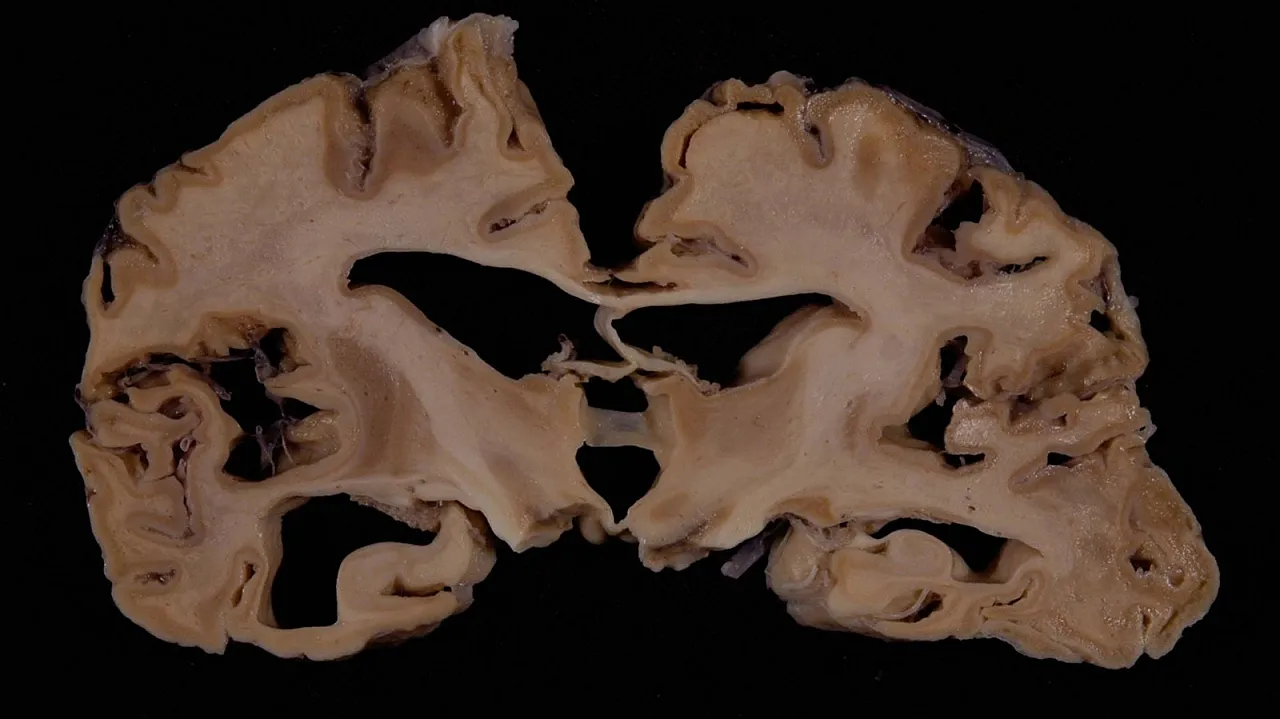

Bolu’da boğaz ağrısı, mide bulantısı ve baş dönmesi gibi şikayetlerle İzzet Baysal Hastanesi’ne başvuran bir kadında gerekli incelemeler yapıldı. Z.A.’nın beyin dokusunda deli dana olarak bilinen hastalık tespit edildi. Teşhis konulan kadının tedavisinin sürdüğü belirtildi.

Deli dana hastalığı, bulaştığı kişilerde sinir sistemini aşama aşama yok ediyor. Unutkanlıktan başlayarak el-kol koordinasyonu bozukluğuna kadar pek çok şekilde görülen deli dana hastalığının ileri safhalarında felç ve ölüm sonucu ile karşılaşılıyor.